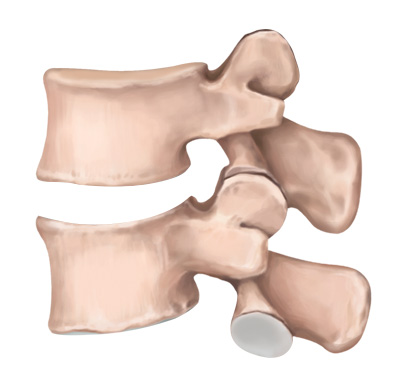

손상된 디스크

STEP 02

손상된 디스크 제거